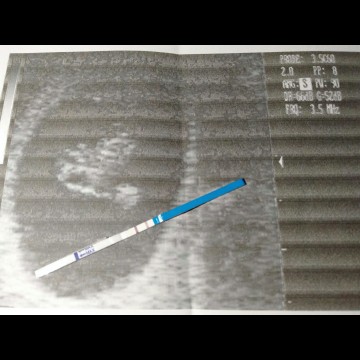

usg

Menurut bundaaa ini gimana??

Maunya bunda gimana? Dikemasannya sudah dibaca bun?? 😊